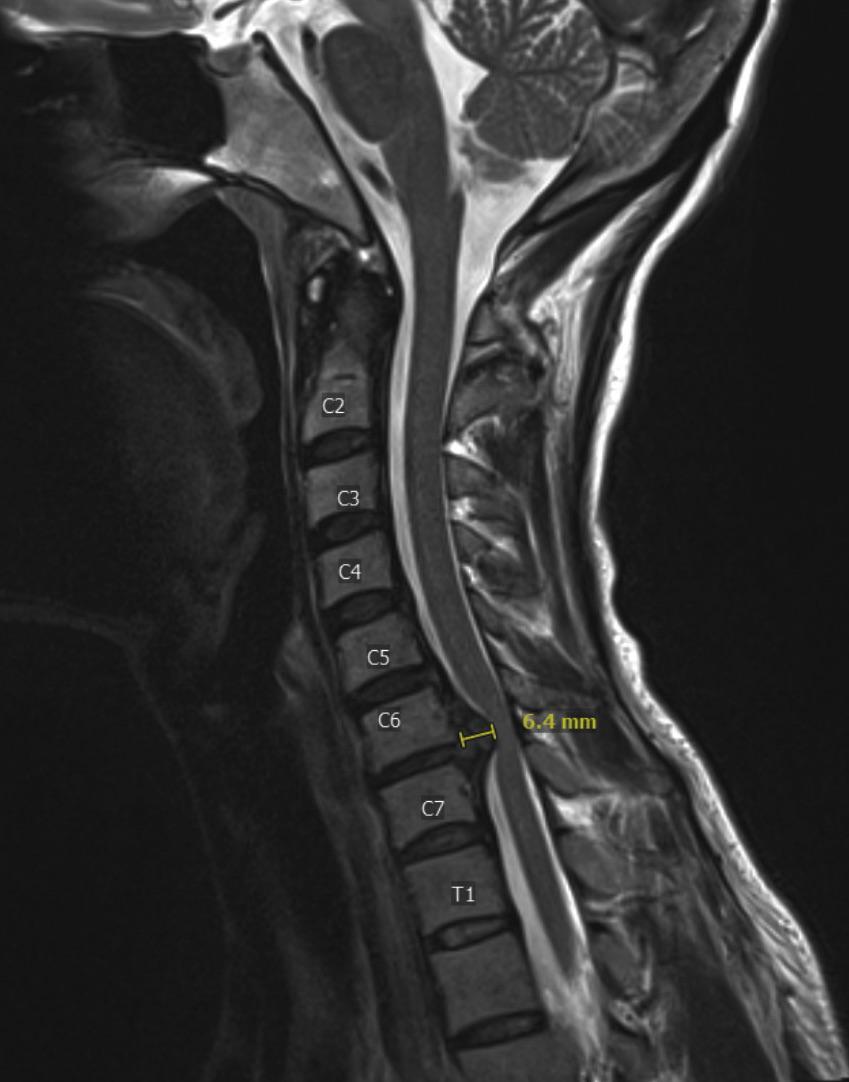

From www.researchgate.net

T2 sequence MRI illustrating the C6C7 cervical disc herniation and How Do You Sleep With A Herniated C6 C7 Here are some tips that may help you enjoy a more peaceful night of sleep: A properly aligned spine can decrease pressure on the back and reduce discomfort. An adequate period of sleep, with good quality of sleep, is very important to manage pain successfully. This neutral position reduces the chances of you pinching the nerve. The best sleeping position. How Do You Sleep With A Herniated C6 C7.

T2 sequence MRI illustrating the C6C7 cervical disc herniation and How Do You Sleep With A Herniated C6 C7 If you have been losing sleep to a herniated disc, it may be time to pay attention to your sleeping position. Light stretching, with your doctor’s approval, can help. Bad sleeping habits or poor posture can cause severe pain. The best sleeping position for herniated discs can help you maintain. This neutral position reduces the chances of you pinching the. How Do You Sleep With A Herniated C6 C7.